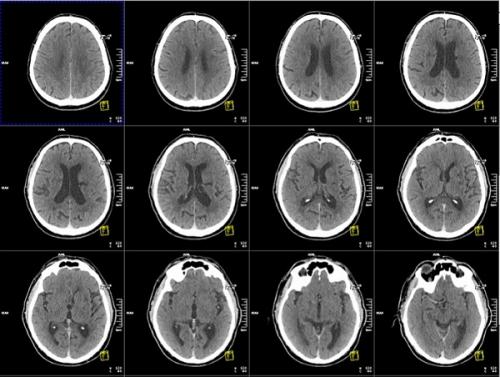

- Для диагностики проблем с сосудами головного мозга применяются различные методы, включая ультразвуковое сканирование сосудов, ангиографию, компьютерную томографию, магнитно-резонансную ангиографию.

Используются методы нейровизуализации. Они позволяют врачу осматривать артерии и сосуды в головном мозге и вокруг него, а также саму ткань головного мозга. К ним относятся:

- КТ/ МРТ головного мозга;

- КТ/МР- ангиография головного мозга;

КТ головы

Компьютерная томография (КТ) — это метод исследования, основанный на воздействии рентгеновского излучения на организм. По сути речь идет о более "продвинутом" и более информативном варианте классического рентгена. Компьютерная томография, в основной части случаев, сильно уступает магнитно-резонансной томографии в информативности.

Дело в том, что МРТ лучше визуализирует мозговое вещество. КТ же направлена на визуализацию плотных тканей организма. В частности, костей. Потому перечень показаний для такой диагностики ограничен. Среди оснований: